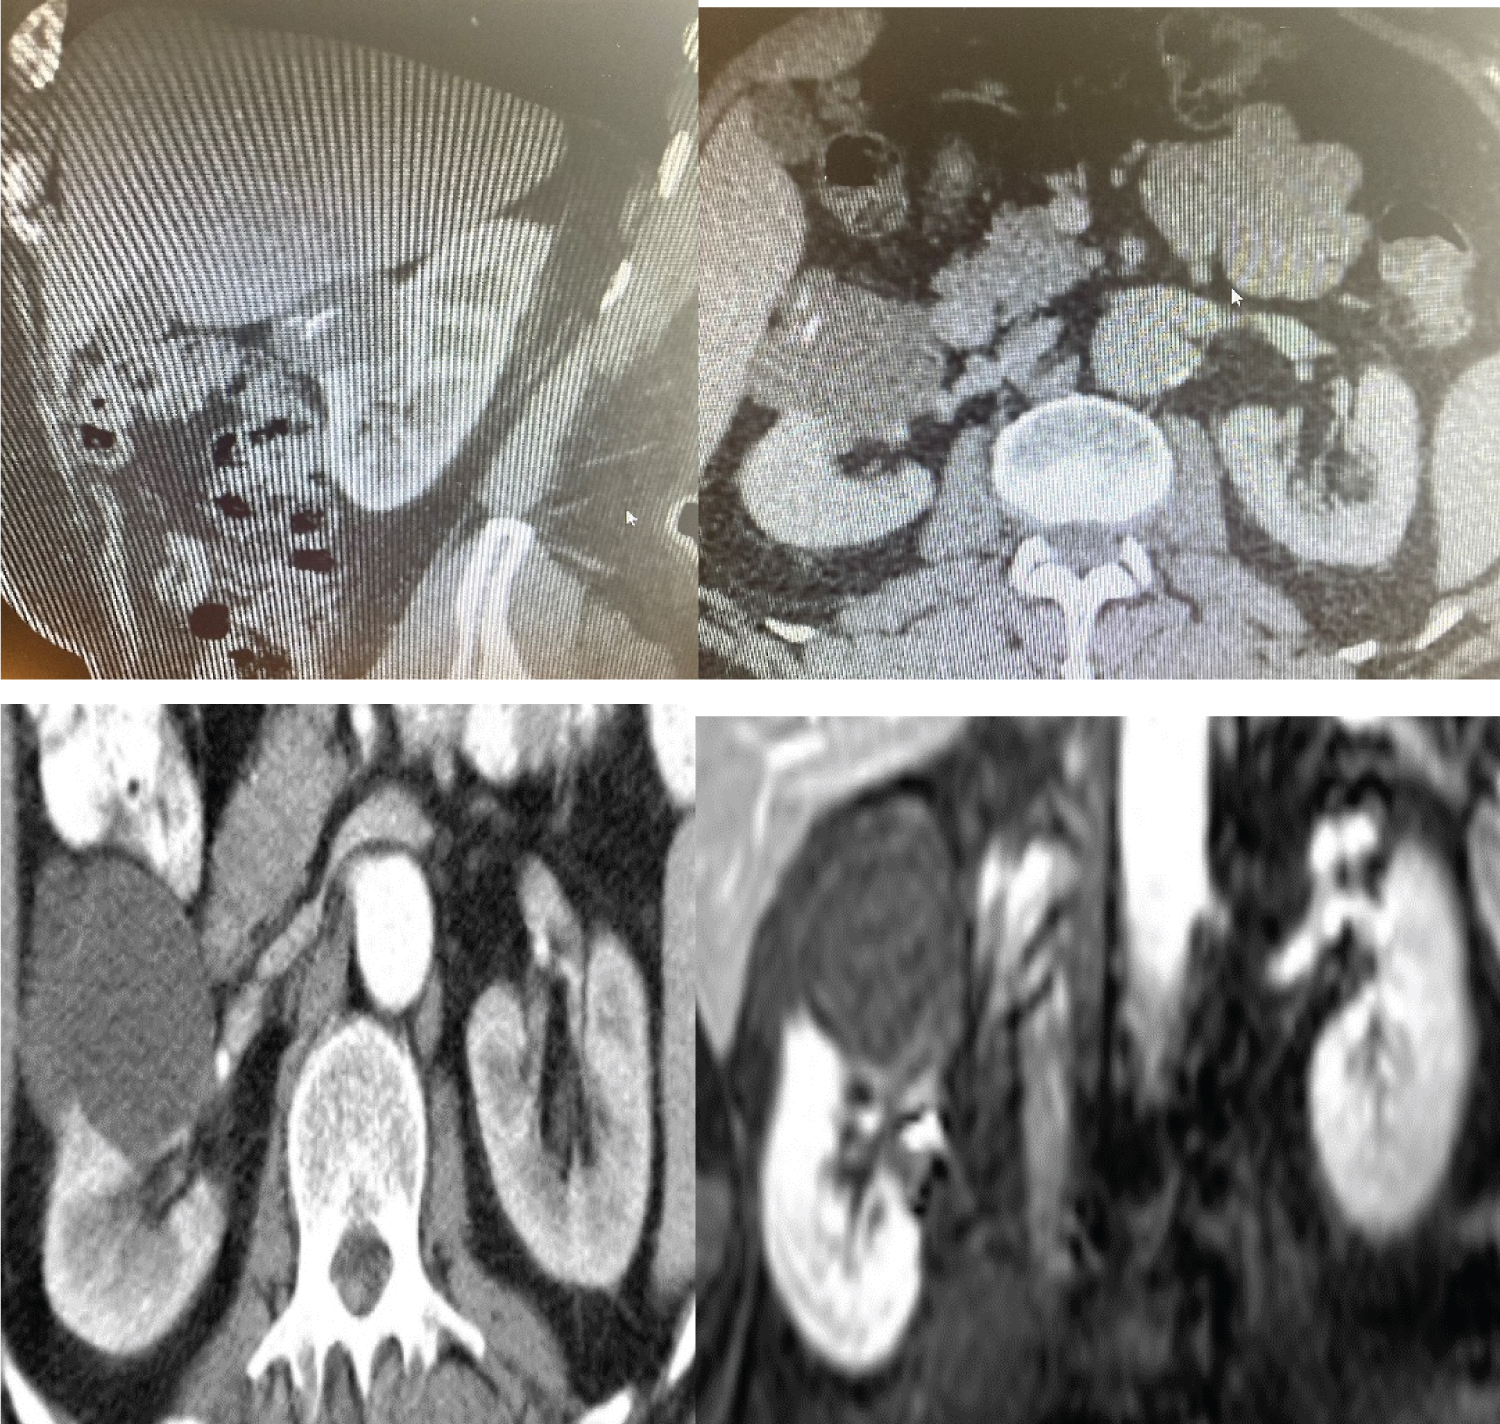

A 72-year-old male patient was admitted to our urology clinic after a right renal mass was detected in abdominal ultrasonography performed due to hematuria. A computed tomography (CT) scan was performed on the patient before the surgery. In the patient's entire abdominal tomography examination, a multilocular cystic lesion was observed in the upper pole of the right kidney, containing parapelvic and exophytic components, reaching 50 × 51 × 50 mm in size at its widest point, and containing thin septa in the anterior and slight contrast enhancement and millimetric-sized calcification in the septa (Figure 1). This cystic lesion was evaluated as type 3 according to the Bosniak classification. The patient underwent transperitoneal laparoscopic right radical nephrectomy. After pathologic examination, a diagnosis of CN was made. In CN, which consists of cysts and septa, epithelial cells in the form of hobnail and a tubular structure in the septa were seen (Figure 2 and Figure 3). During the 2-year follow-up of the patient, no additional treatment was given, and no local recurrence or metastasis was observed. The patient was informed about the case presentation and written consent was obtained for the publication of the case and the use of their images.

Figure 1: CT image of multilocular cystic lesion, separated by thin septations. View Figure 1